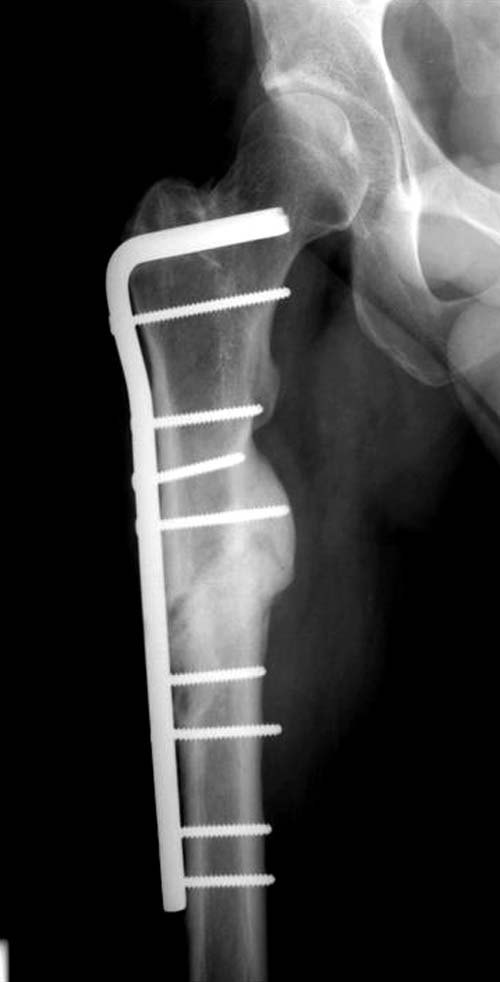

Имя     : 2 Fem nonunion lat preop.jpg

Тип     : image/jpg

Размер  : 25403 байтов

Описание: отсутствует

Url     : http://weborto.net:8080/pipermail/ortho/attachments/20111214/0c6bb1fc/attachment-0005.jpg

Нестабильность не только дистальных винтов, а также всей конструкции, которая свободно плавает внутри канала. Болтающийся штифт, сильные боли при ходьбе, а также отсутствие консолидации напоминает клиническую картину инфекцию канала. При подтверждении инфицированного ложного сустава лабораторно или клиническими исследованиями дальше по протоколу: промывание и риминг, временнный спейсер с антибиотиком и окончательная фиксация после разрешения процесса.

Тактика замены на более толстый гвоздь вроде правильная, и возможно у Вас получится с первого раза. Но без специальных трюков гвоздь удержать трудно, потому что между точкой на верхушке трохантера и старым каналом в пириформис почти отсутствует стенка. Без стенки трудно удержать гвоздь латерально и без блокирующих приспособлении гвоздь найдет старый канал. Конечность поведет и винт в головке срежется. Без опыта проведении блокирующих спиц, о которых  говорит Александр, вся затея окажется фиаско! Отклоняющие в передне-заднем направлении спицы в проксимальном отделе бедра немного страшновато, с повреждением седалищного нерва!

Поэтому хотел предложить альтернативную технику, открыть место ложного сустава субвастус доступом и кортикотомия, одномоментное удлинение, аппозиция латерального кортекса. Для фиксации Blade Plate с коротким клинком при возможности или обычная прямая преконтурированная 4.5 мм пластина с медиальным костным графтом.

По-моему, такая простая техника решит проблему склерозированного старого ложного сустава намного дешевле, чем гвоздь, и без необходимости обьязательного ЭОПпри установке Гамма.